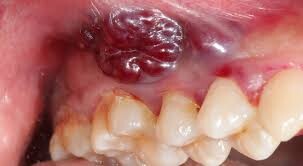

Cancer is another area that can cause bumps in the mouth. There are many types of this disease that manifest in the mouth. As with any cancer, these can be very difficult to treat. Early detection and treatment are most important to give the patient the best chance of a full recovery.